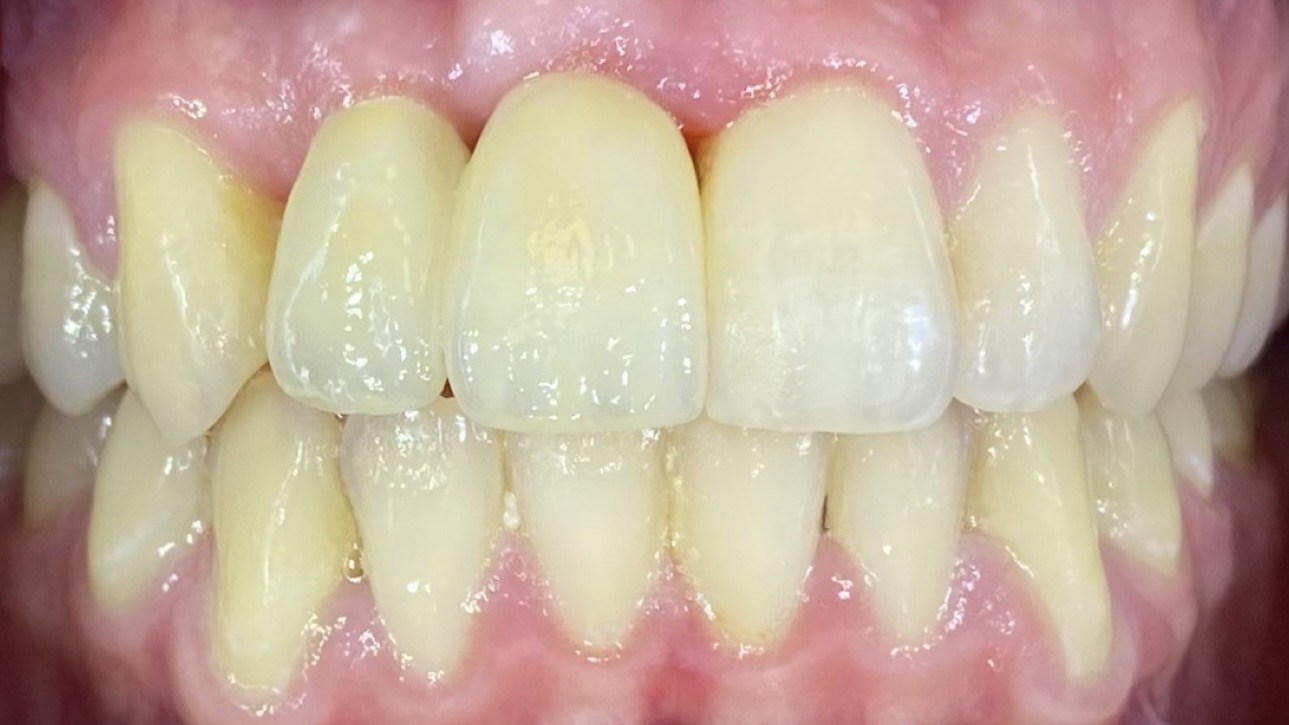

The poster provided a clear and structured overview of the pre-, intra-, and postoperative stages of ceramic implant placement, illustrating:

the dynamics of soft- and hard-tissue healing,

and the long-term functional and aesthetic outcomes achievable with ceramic implants.

The presentation highlighted why biologically driven implantology — combined with precision, minimally invasive protocol selection, and ceramic biocompatibility — is setting new standards in patient-centered care.